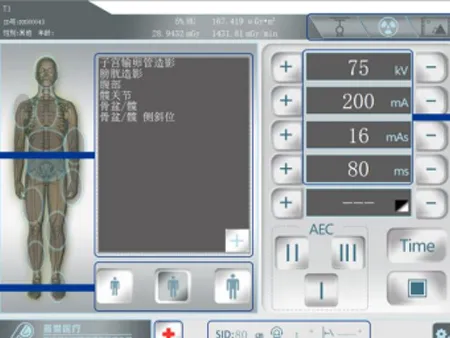

El sistema radiográfico incluye una pantalla táctil de 10.4 pulgadas y una estación de trabajo completa con monitor, joystick, software de última generación de imagen y controles ergonómicos, lo que simplifica la operación y mejora el flujo de trabajo. Con este equipo, podrá enfocarse en lo más importante: ofrecer diagnósticos certeros y una atención médica de calidad.

- Registro de pacientes: Realice registros estándar o de emergencia de forma rápida. También puede agregar acuerdos y estudios específicos, editar o eliminar información, e iniciar directamente una inspección si el caso lo requiere.

- Lista de trabajo: Acceda fácilmente al listado de pacientes pendientes por examinar. Busque, actualice, elimine estudios o personalice las columnas para visualizar justo lo que necesita. Desde aquí también puede iniciar exámenes o activar el modo de emergencia según la situación.

- Historial de exámenes: Revise la información de pacientes ya atendidos, visualice imágenes, búsquelas por nombre o fecha, elimínelas si es necesario, guárdelas o incluso grabe CD con los resultados. También podrá añadir nuevos estudios o ajustar los datos del examen de manera sencilla.

- Configuración según el paciente: El sistema permite seleccionar el tipo de complexión: adulto delgado, promedio o corpulento, para ajustar la exposición de forma más precisa.

- Parámetros de imagen (fotografía): Personalice el proceso seleccionando el modo de exposición, velocidad de fotogramas, valores de kVp, mA, ms, mAs, AEC o el tipo de enfoque.

- Parámetros en modo de perspectiva (fluoroscopía): Configure también este modo ajustando el tipo de exposición, velocidad de imagen, kVp, mA, control automático (ABS) y tiempos de reinicio.

- Pantalla táctil inteligente junto a la mesa ermitiendo el control total del eequipo.

- Ideal para agilizar tanto estudios programados como emergencias sin necesidad de repetir configuraciones.

- Previsualizar las imágenes justo después de la exposición.

- Ver en tiempo real la distancia SID (foco-imagen).

- Regula fácilmente todos los parámetros de exposición.

- Elegir la zona del cuerpo a examinar con ayuda de ilustraciones anatómicas.

- Controlar con precisión el área del colimador.

- Visualizar digitalmente el ángulo de rotación del cabezal del tubo.

- Guiarte con una demostración de posicionamiento en modelo 3D.

- Beneficiarte de su sensor de gravedad con rotación automática para mayor comodidad.

- Acceder rápidamente a exámenes de urgencia: toma la imagen de inmediato y completa los datos del paciente después.